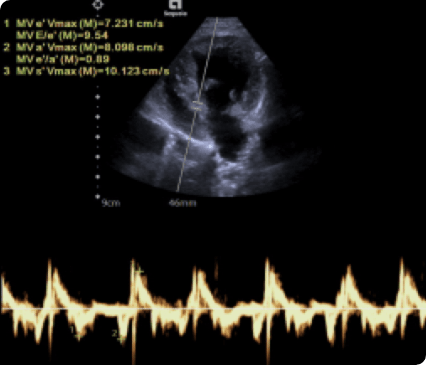

최고사양의 Siemens Sequoia 초음파 장비를 갖추고 있습니다.

일산시티동물의료센터는 최신 고해상도 초음파 장비를 통해 세밀하게 심장을 정밀하게 분석하여 심장질환을 진단합니다.

노령견에서 가장 흔한 퇴행성 심장질환으로,

판막의 기능 저하로 인해 혈액이 좌심방으로 역류하면서

심비대, 폐수종, 심부전까지 유발할 수 있는 질환.